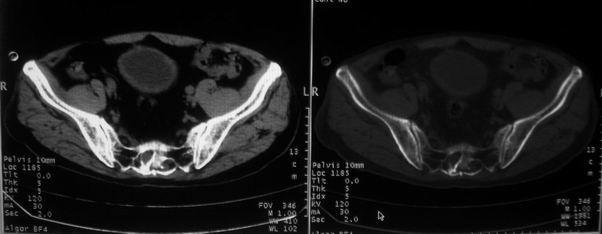

男,85岁,排尿困难。骶椎有问题吗?

前列腺明显增大,突入膀胱,各叶比例协调,密度均匀,精囊腺及精囊角正常;考虑良性增大。

骶骨没有看到明显异常。

1)前列腺明显增大,突入膀胱,各叶比例协调,密度均匀,精囊腺及精囊角正常;考虑前列腺增生症并阻塞性膀胱炎。2)骶椎右侧类似囊状骨质密度减低区,边缘骨质硬化,其内为软组织密度影填塞,相邻之骶椎椎管受压变形;考虑为骶椎右侧囊肿或神经纤维瘤。

建议:行mri检查。